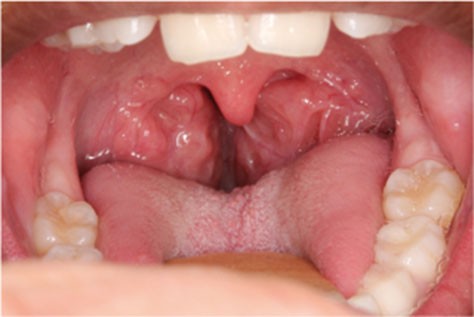

Il est classique de distinguer trois profils différents d’enfants susceptibles d’avoir un SAOS :

– les enfants présentant un obstacle ORL (les plus nombreux) : typiquement, il s’agit d’une hypertrophie des amygdales (tonsilles) palatines (fig. 1) ;